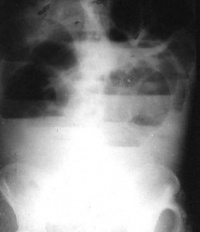

结肠梗阻

CT平扫见结肠肠腔扩张及结肠内气液平。

结肠梗阻CT平扫